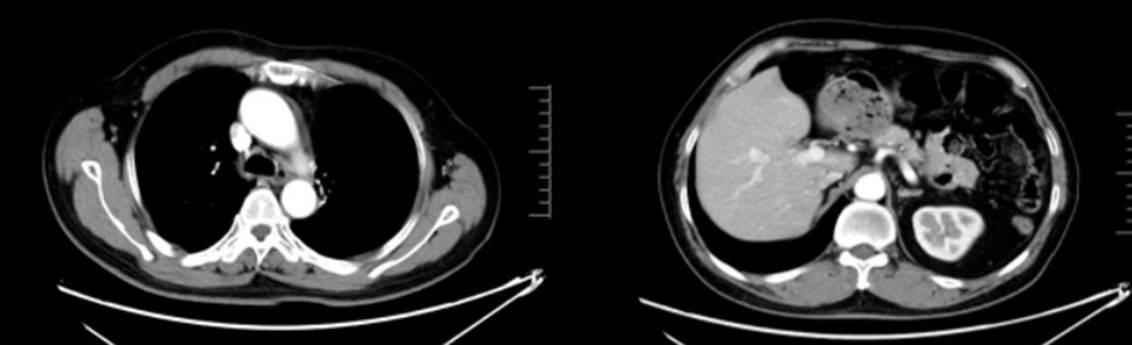

2024年12月9日(14月后):左残肺及右肺结节较前明显缩小;

2025年8月19日(22月后):左侧锁骨上区、纵隔及左肺门区多发小淋巴结基本同前,未见明确疾病进展迹象。